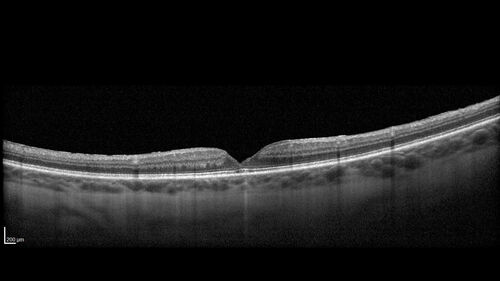

Lamellar Macular Hole and Good Vision

67 year old woman with good vision and floaters - VA 20/32 OD, 20/23 OS